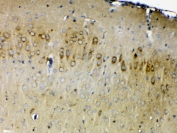

ERBB4 Antibody Mouse Brain IHC. Immunohistochemistry testing of FFPE mouse brain tissue with ERBB4 antibody at 1ug/ml. Required HIER: steam section in pH6 citrate buffer for 20 min and allow to cool prior to testing.